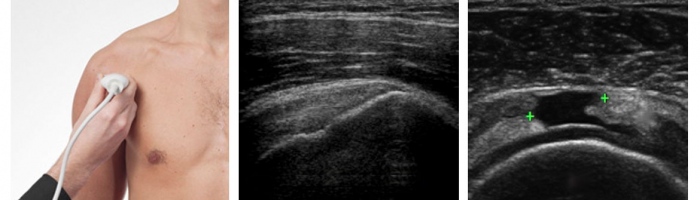

Na co dzień zajmujący się ultrasonografią stawów, mięśni, nerwów obwodowych.

• Kieleckie Centrum Pediatryczne - Gabinet USG nr 27 USG barku  •